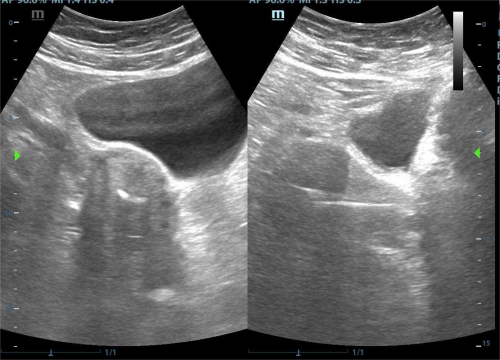

传统取环术依赖术者经验与手感,在应对节育环嵌顿、移位、断裂或绝经后宫颈萎缩等情况时,常因无法准确判断环的位置而导致失败。超声引导技术通过实时动态显示宫腔结构、节育环形态及器械位置,使术者能够精准定位环的具体位置,并引导器械沿正确方向操作,从而大幅提高取环成功率。即使是节育环断裂、残留等复杂情况,超声引导也能通过精准定位实现完整取出。

传统取环因属“盲目操作”,容易引发子宫穿孔、宫颈撕裂及出血等并发症。超声引导通过“可视化”监控器械进入的深度与方向,有效避免器械过度深入或误穿子宫壁;同时能清晰显示节育环与周围组织的关系(如是否嵌入肌层),减少因强行牵拉造成的组织损伤。

传统取环需通过探针反复探测宫腔深度与环的位置,耗时较长,超声引导通过实时显示环的位置,使术者能直接将器械对准环的方向,减少不必要的探测步骤,从而缩短手术时间。